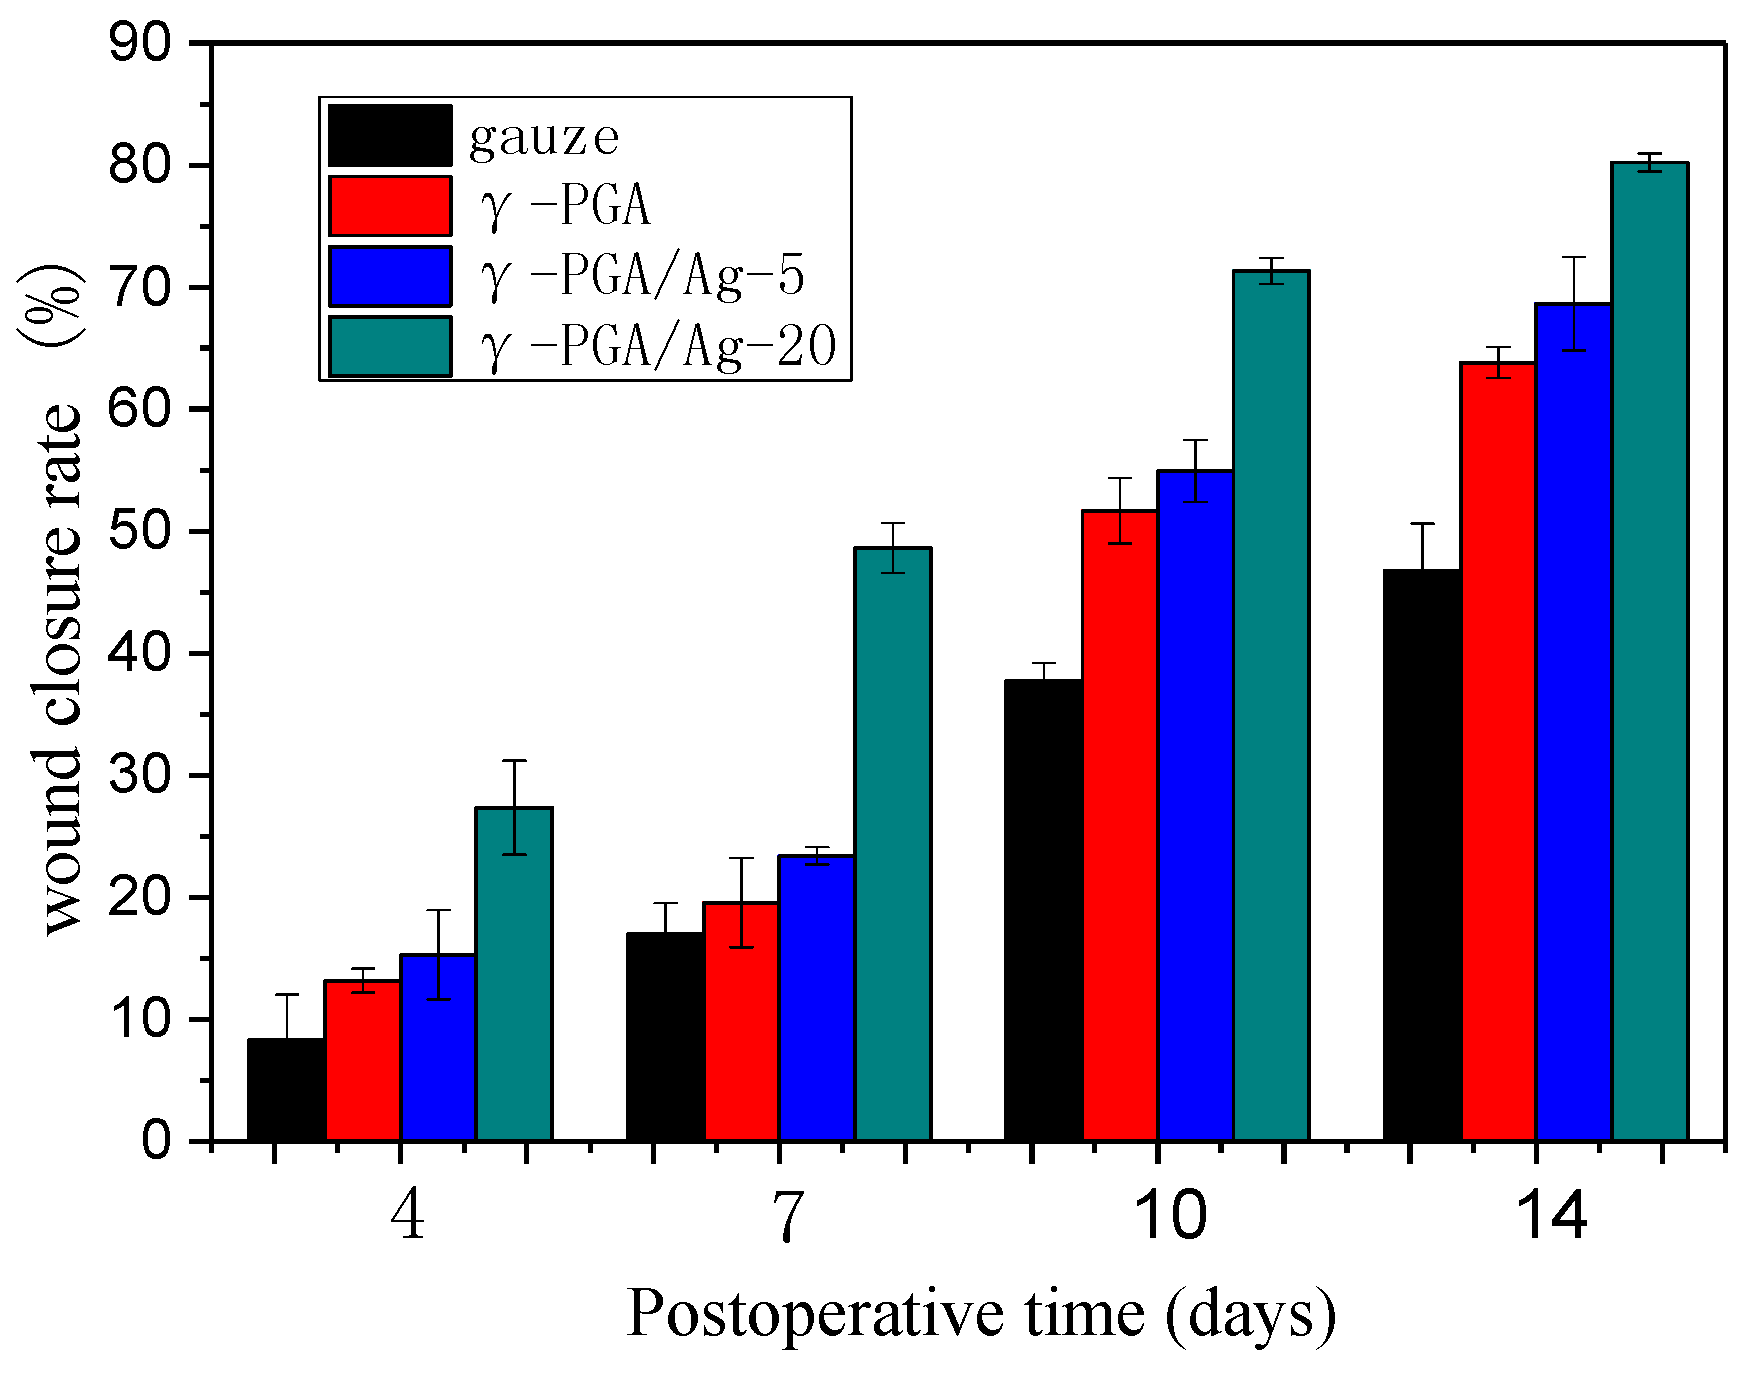

3.4. In Vivo Study